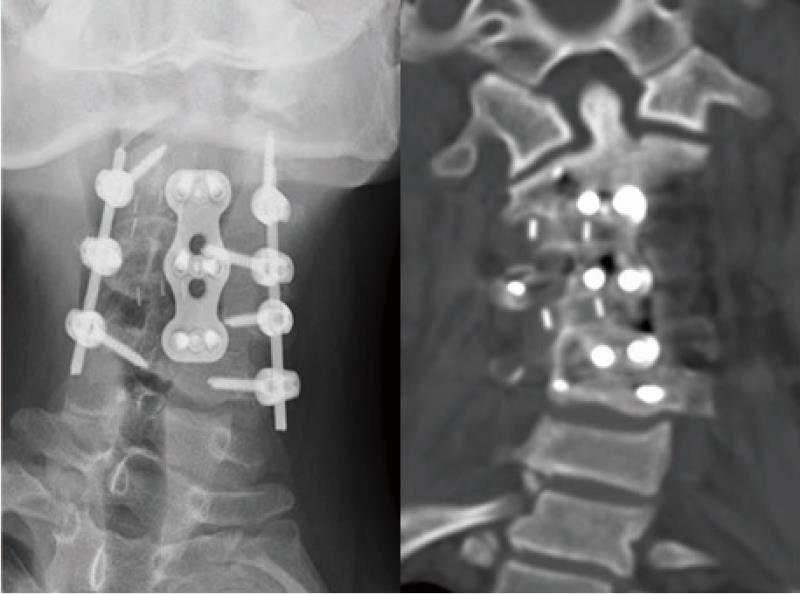

病例1:颈椎人工椎间盘置换术

颈前路C4-6椎间盘切除,Bryan人工椎间盘置换术,术后10年随访活动度良好。